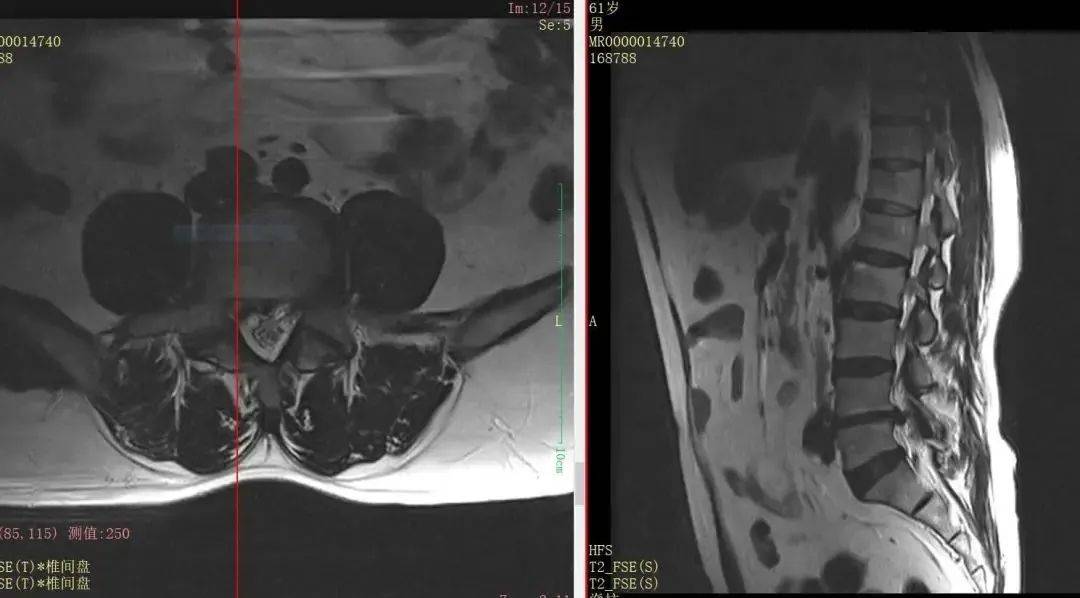

61岁男性,因腰腿痛及双下肢麻木入院,查体示双侧小腿外侧及足底感觉减退(左重)、左直腿抬高试验阳性、肌力下降。影像确诊L4/5右侧椎间盘突出伴左侧髓核脱垂至椎弓根内缘,合并L5稳定峡部裂。

采用数字化虚拟精准重建、规划,导航实现毫米级定位,避免神经损伤,硬膜波动恢复良好。术后验证数字技术可缩短学习曲线,提升复杂病例操作安全性与病灶清除率,为脊柱微创标准化提供新范式。